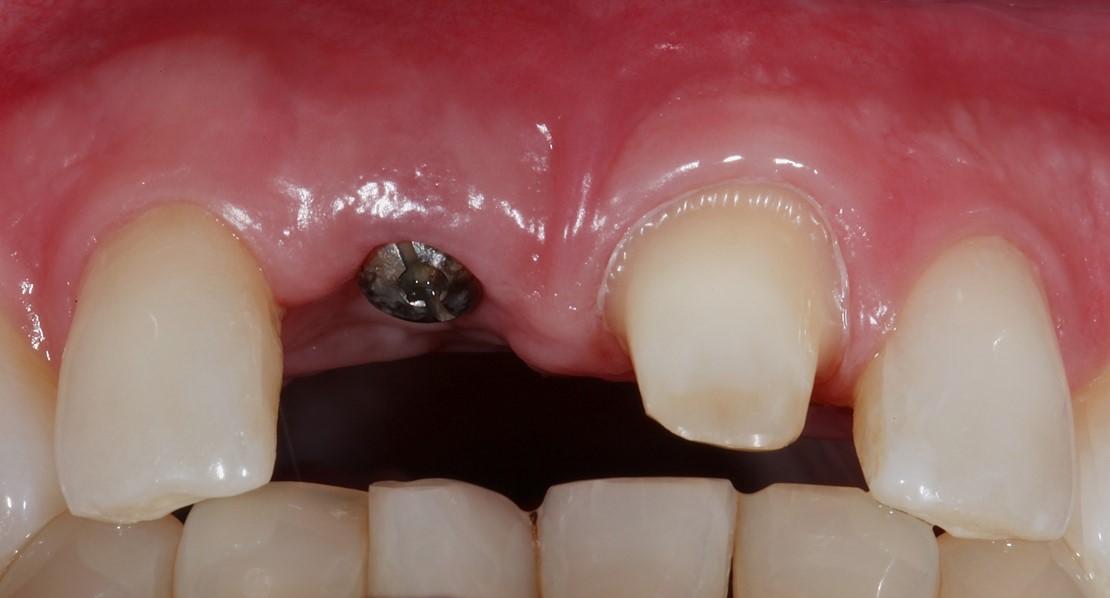

Fig 8. Case 1: A patient presented in January 2006 with a large periapical lesion, a root fracture, and significant buccal bone loss.

Figure 8

Fig 9. Despite the extent of bone loss revealed radiographically, multiple surgical grafting procedures were not indicated. Instead, a flapless surgery would be performed and biologic innovations used to facilitate ridge preservation.

Figure 9

Fig 10. The tooth was extracted; the socket debrided and degranulated; and ridge preservation was performed with FDBA/rhPDGF and an absorbable membrane.

Figure 10

A patient presented with a large periapical lesion, root fracture, and significant loss of buccal bone (Figure 8 and Figure 9). Treatment for this case involved an autogenous bone graft, then implant placement and connective tissue grafting. Recombinant human platelet-derived growth factor-BB was used for ridge preservation and minimally invasive esthetic implant site development with a flapless approach.

The tooth was extracted, and magnification was used while debriding and degranulating the extraction socket. The site was irrigated with a significant amount of sterile water from 10-mL syringes, and the water pressure helped with debridement. Spoon and #4 Gracey curettes were used.

Once degranulated and debrided, the growth factor matrix (eg, freeze-dried bone allograft that was presoaked in rh-PDGF-BB for about 10 minutes) was condensed into the site. The site was then covered with a collagen membrane and sutured.

After healing, the site was evaluated and a high frenum attachment was observed (Figure 10). A frenectomy was performed prior to implant placement, along with a connective tissue graft to thicken the soft tissues.